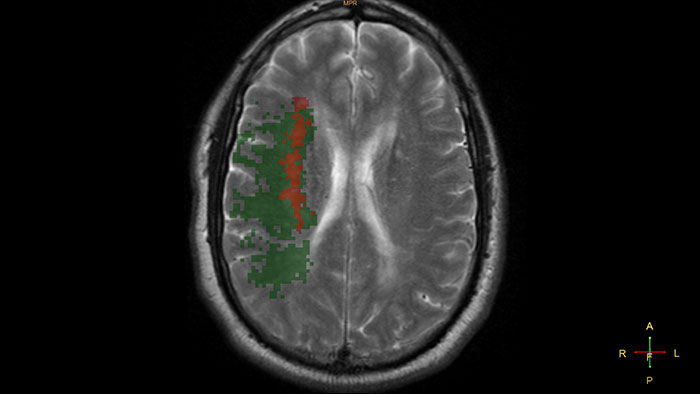

Reviewing brain tissue viability

MR T2* (Neuro) Perfusion is designed to assess brain perfusion helping with stroke assessment and other disease tracking. Visualization and quantitative analysis of the diffusion-perfusion mismatch in case of acute stroke is also included.

Benefits